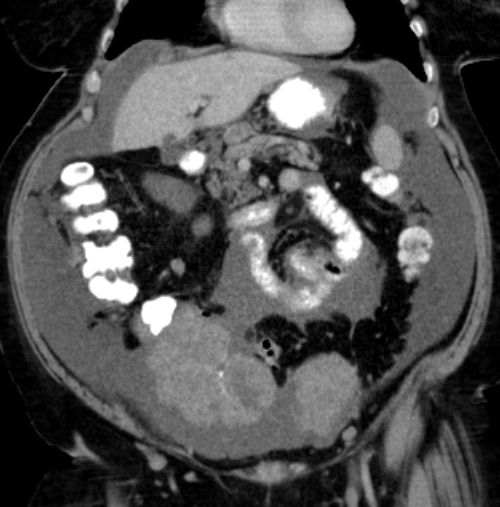

73-jährige Frau mit Ascites, Pleuraerguss links und Unterbauchtumor.  Das Netz ist komplett in einen Omental-Cake umgewandelt. An der Zwerchfellkuppe miliare Tumoraussaat.

Beide Adnexe in knapp kindskopfgroße blumenkohlartige Tumoren umgewandelt.

Im Douglas finden sich pararektal mehrere bis zu pflaumengroße Tumorknoten.